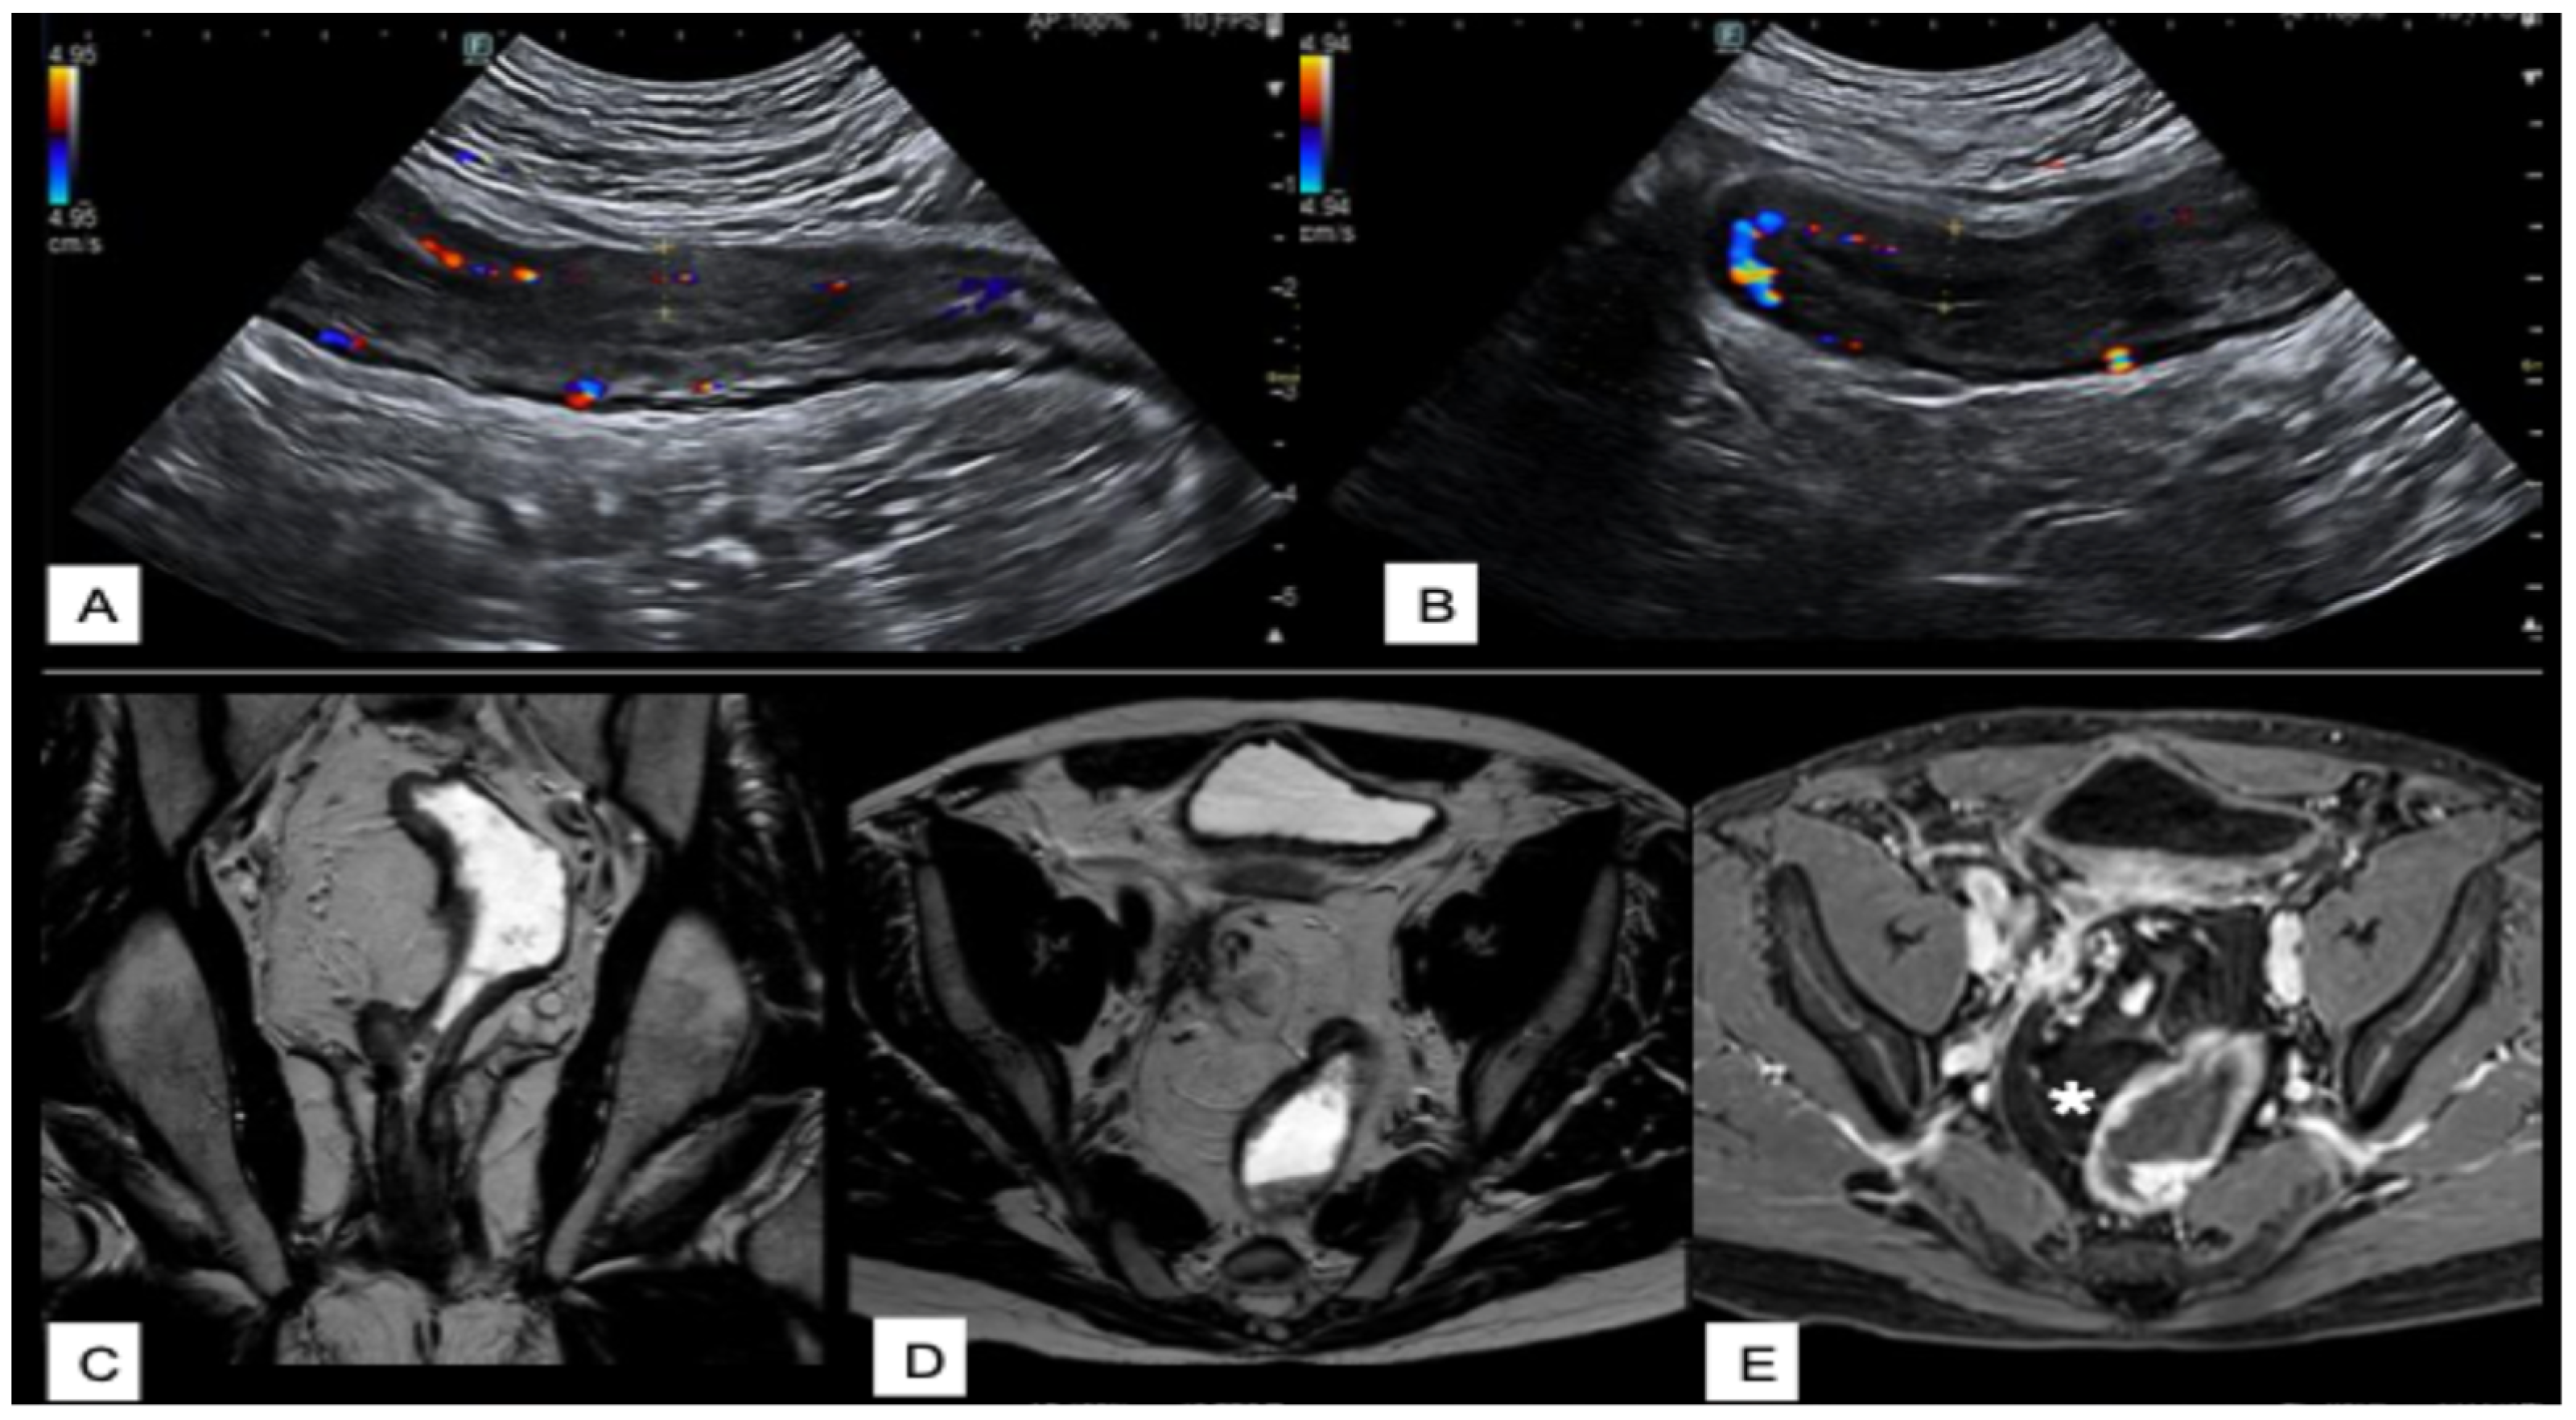

Intestinal Ultrasounds Imaging Findings and Scoring Systems

3.4.2. Typical MRI Findings in Crohn’s Disease

3.4.3. Typical MRI Findings in Ulcerative and Indeterminate Colitis